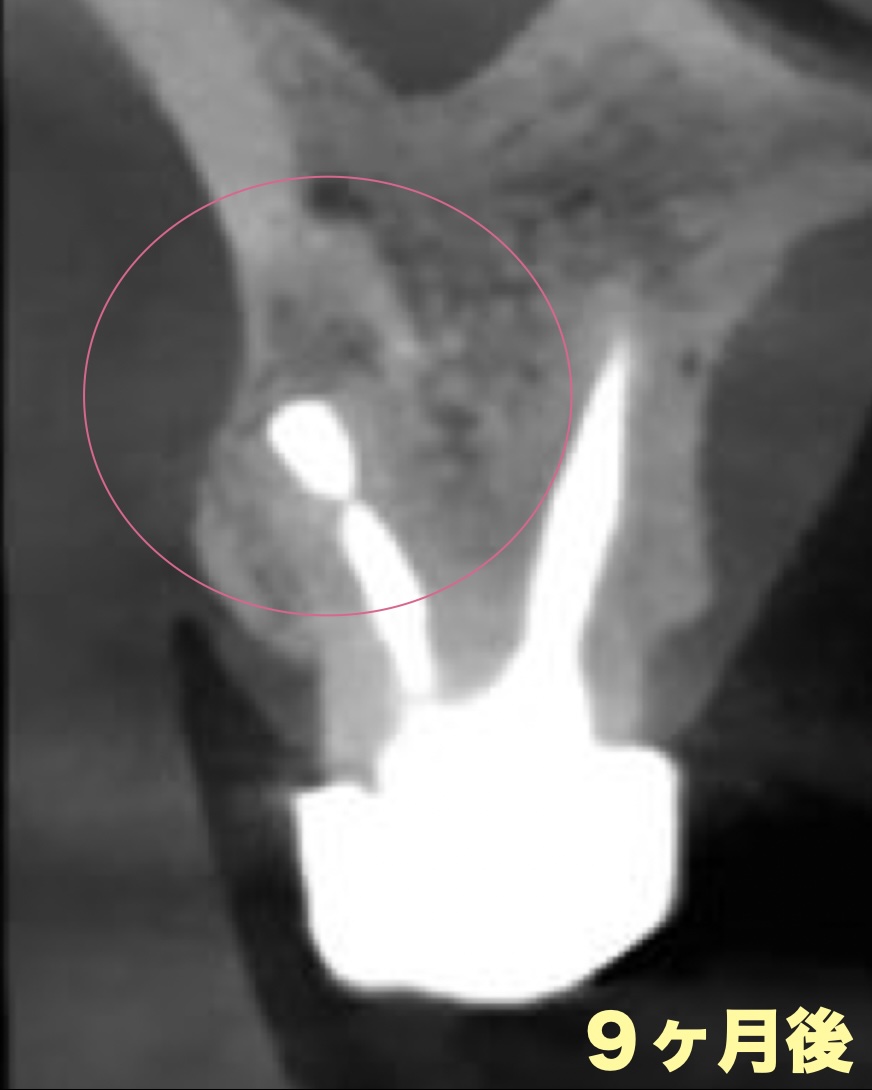

手術前は、歯の根の先に黒い影があり、骨が溶けている部位が確認できました。

9ヶ月後にはその部分が白くなり、骨が再生していることが分かります。

黒い部分は骨が溶けていた部位、

白くなった部分は骨が再生した部位です。